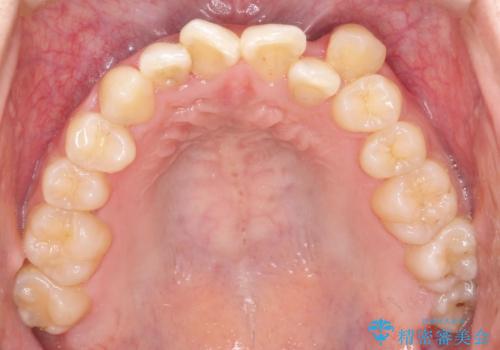

- 患者様は左上の八重歯を気にされて来院されました。八重歯による歯列の乱れだけでなく、翼状捻転(歯がねじれるように生えている状態)も見られました。目立たない矯正を希望されていたため、**インビザライン(マウスピース矯正)**を選択し、左上の小臼歯を抜歯してスペースを作りながら歯を並べる治療計画を立てました。しかし、治療の途中で翼状捻転の改善が十分に進まなかったため、患者様の希望も踏まえ、上顎のみワイヤー矯正に変更することとなりました。

治療開始時はインビザラインを使用し、全体の歯並びを整えながら抜歯スペースを活用して歯を後方へ移動させました。しかし、左上の八重歯のねじれが強く、マウスピースのみでは十分にコントロールできないことが判明。そこで、より細かく歯を動かすために上顎のみワイヤー矯正へ切り替えました。ワイヤー矯正によって翼状捻転も改善し、最終的にバランスの取れた歯並びと噛み合わせを実現。患者様からは「長い治療だったけれど、しっかり整って満足」と嬉しいお言葉をいただきました。